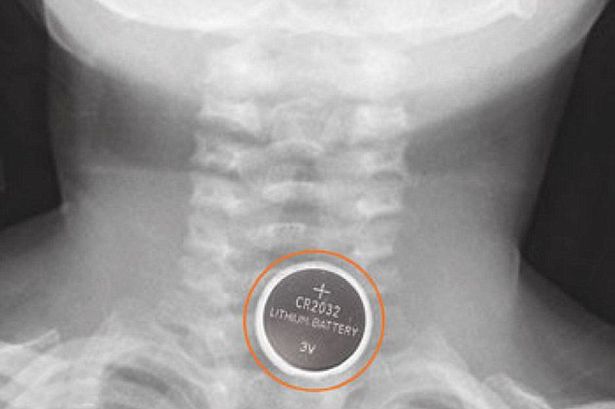

Người ta ước tính khoảng 260 trẻ em nuốt pin lithium mỗi năm tại Úc. Khi nuốt phải những cục pin, chúng có thể gây ra phản ứng hóa học đối với tuyến nước bọt và đốt cháy các mô ở bên trong cơ thể, gây nguy hiểm đến tính mạng của trẻ.